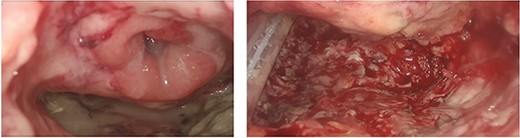

A 75-year-old Caucasian man was referred to our department on May 2022 because of a positive fecal occult blood test; subsequent colonoscopy showed an endoluminal substenosing lesion, located at sigmoid-rectal junction and extended distally for 5 cm. The tumoral bulk appeared centrally ulcerated and occupied more than three-fourth of the rectal circumference. The panel of biopsies resulted positive for well-differentiated adenocarcinoma. An angio-CT scan confirmed the presence of a sigmoid-rectal wall thickening, extended distally for about 6 cm, with significative narrowing of colonic lumen. Lateral spread appeared limited to the muscolaris propria, whereas the mesorectal component was unaffected; the presence of T2 lesion at preoperative diagnostic work-up was confirmed by MRI while neither hepatic nor pulmonary metastasis were detected. Tumor markers were within normal range. At physical examination, the patient appeared overweight (BMI 30.5), with no other significative comorbidity. Pre-operative staging led the Multidisciplinary Tumor Board to authorise a surgical approach. The patient underwent laparoscopic low anterior rectal resection with total mesorectal excision, with transanal end-to-end stapled colorectal anastomosis (7 cm from the anal verge) and ileostomy. Histological report of resected specimen confirmed the diagnosis of a G2 rectal adenocarcinoma, staged as pT3 pN1a R0, whereas the quality of mesorectal excision was graded as 3 (complete mesorectal fascia) according to Quirke classification. On the fifth post-operative day, the patient developed an increase in body temperature (37.8°C), in WBC count (10 × 103/uL) and in CRP plasmatic levels (6.63 mg/dL), as well as a corpuscular discharge from perianastomotic drainage; at physical examination, the patient showed a moderate tenderness on lower left abdomen with no clear signs of peritonitis. Early abdominal angio-CT scan showed a 15-mm discontinuity on the posterior wall of colorectal anastomosis, with perirectal fluid and extraluminal gas collection (Fig. 1). Low-flow endoscopic exploration confirmed the anastomotic wall defect in the right postero-lateral side, connected to a cavity filled with necrotic tissue (Fig. 2). Given the presence of ileostomy and perianastomotic surgical drainage and the absence of peritonitis signs with proper control of patient’s hemodinamics, we opted for a non-surgical treatment. On the sixth post-operative day, the patient underwent an Endo-SPONGE® device placement into the AL cavity, performed with TAMIS approach [7]. With the patient in lithotomy position, a GelPOINT® path transanal access platform was positioned; laparoscopic insufflation pressure was set at 10 mmHg. The right posterolateral anastomotic wall defect was visualised (Fig. 3), then the AL cavity was carefully measured (3 cm × 4 cm), washed with saline solution and explored up to the tip of surgical drainage. The polyurethane sponge was positioned under laparoscopic vision and then connected to the vacuum suction system, set at −40 mmHg. The Endo-SPONGE® device was replaced every 72 h for 2 weeks, then every 96 h for another 10 days; size and shape of the device were modified and gradually reduced according to the decreasing size of the cavity. Control CT scan and rectosigmoidoscopy confirmed the almost complete obliteration of the AL cavity. The Endo-SPONGE® device and the abdominal drainage were removed on the 25th post-operative day and the patient was then discharged without further complications. The patient has been addressed to adjuvant treatment protocol; a 3-month control CT scan showed neither distant metastases nor residual perirectal cavity. Once adjuvant treatment is completed, patient will be enrolled for colorectal anastomotic check and closure of ileostomy.

Low-flow endoscopic exploration which confirmed the presence of dehiscence of the colorectal anastomosis in the right postero-lateral colonic wall, 7 cm from the anal verge, giving access to a large cavity filled with fibrin and necrotic tissue (yellow arrow), colic lumen (blue arrow).